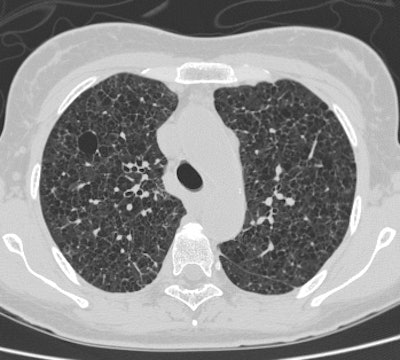

34 year old female patient presented with increasing SOB and underwent CTPE examination. PE exam revealed scattered small nodules and findings that were felt to be related to very advanced emphysema vs cysts. HRCT exam was recommended.

CT PE exam revealed no evidence of PE, but demonstrated findings suggestive of advanced emphysema versus cysts. A few small nodules were also identified within the lungs (arrow). |